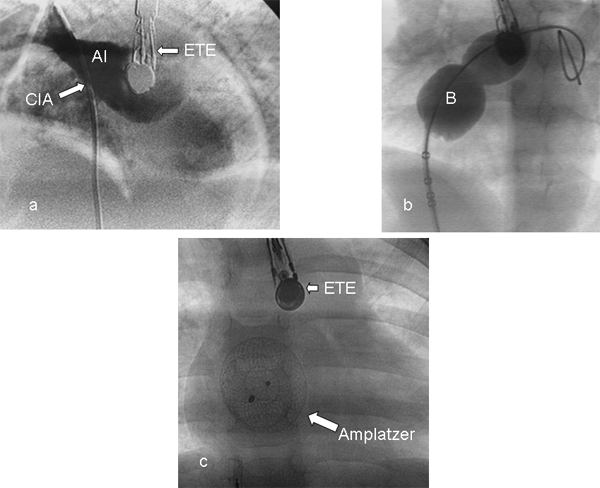

Desde los trabajos iniciales de King y Mills en los años 70 existe la posibilidad de cerrar las comunicaciones interauriculares tipo ostium secundum mediante cateterismo. Muchos dispositivos se han diseñado desde entonces a tales efectos, pero pocos han perdurado, siendo los más usados en el momento actual los dispositivos Amplatzer ASD que constan de dos discos unidos por un cuello central y rellenos de parches de poliéster (el izquierdo de mayor tamaño, construido en una malla de nitinol: aleación de níquel y titanio, material caracterizado por ser maleable, con la resistencia del metal y tener la propiedad de memoria, es decir se le otorga una determinada forma, se lo introduce a través de una vaina en el momento de su colocación, es desplegado y tiene la posibilidad de ser reenvainado si no queda en una posición correcta y vuelto a desplegar, pudiendo ser retirado sin inconvenientes antes de ser liberado). Otros dispositivos son el Hélex y el Cardioseal. El tamaño del dispositivo se elige habitualmente de acuerdo a las medidas realizadas con catéter balón efectuadas mediante fluoroscopía y ecocardiograma Doppler color transesofágico (ETE). Algunos utilizan el ecocardiograma intravascular (EIV) o transtorácico (ETT). La selección de los pacientes pasibles de ser beneficiados mediante el cierre por cateterismo se analiza en la tabla 3. El tamaño máximo del defecto que puede ser cerrado está en discusión, pero debemos considerar que a mayor tamaño del defecto a cerrar, mayor tamaño del dispositivo a utilizar, lo cual implica riesgo de protrusión de los discos atriales en el techo auricular con posibilidad de erosión hacia el pericardio con producción de un taponamiento o hacia la aorta, creando una fístula aorto-auricular. Luego de verificada por ecocardiograma Doppler color (EDC) la factibilidad de llevar a cabo el procedimiento, se administra heparina a 100 unidades/kg, accediendo por vía venosa femoral. Los datos se corroboran insertando un catéter balón medidor que permite seleccionar el tamaño del dispositivo adecuado a las características del defecto. Esta maniobra se controla por EDC estableciendo, en el momento del cese del shunt desde la aurícula izquierda a la derecha, el diámetro estirado del defecto. Esta medida permite seleccionar el tamaño del dispositivo a utilizar, que debe ser 2 mm mayor que el tamaño de la CIA. Luego se coloca una vaina en aurícula izquierda, extremando los cuidados para evitar la introducción de aire, se ensambla el dispositivo elegido y se lo introduce a través de dicha vaina, desplegándolo en el sitio correspondiente, controlando por EDC su correcta posición y la ausencia de compromiso de estructuras vecinas. Cumpliendo esos requisitos se lo libera, realizando los mismos controles posteriormente. Se hace cobertura antibiótica y el alta se otorga a las 24 horas con antiagregación plaquetaria que se mantiene por 6 meses. Puede persistir un shunt residual habitual las primeras horas. La tasa de éxitos tiene una relación directamente proporcional con la experiencia del grupo tratante con una tasa de complicaciones muy baja, siendo las más temibles:

Estudios comparativos entre cierre quirúrgico y por catéter han demostrado una eficacia comparable entre ambos con menor morbilidad al utilizar la técnica percutánea (figura 4) (7-22).